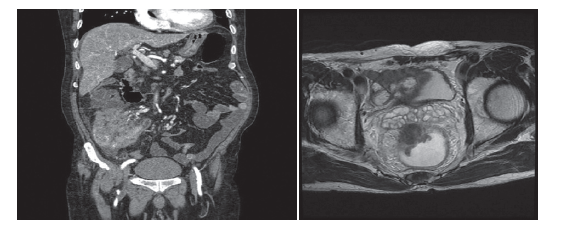

🥈 골반 MRI

→ 종양 깊이·림프절 평가(직장암 병기 결정에 최적)

🥉 직장 초음파(EUS)

→ 국소 병기(T·N) 정확히 평가

🔹 CT(흉·복·골반)

→ 폐·간 전이 확인